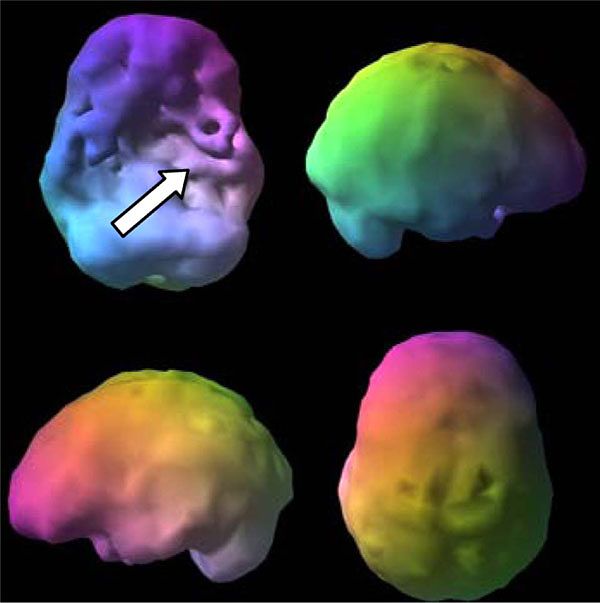

[Picture]

An example of an inmate's SPECT Scan: Shriveled appearance and bumps that signal an unhealthy brain, leading to an unhealthy state of mind.

Another inmate's SPECT scan: Trauma to the frontal and temporal lobes (impairing executive function, memory, and emotional regulation).